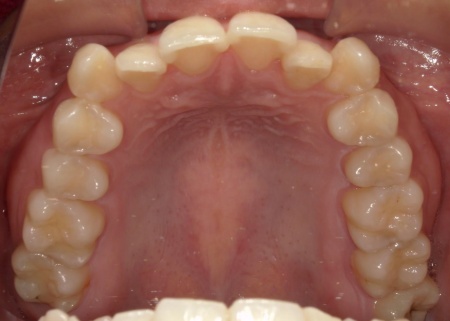

20代女性 八重歯と歯並びの乱れをマウスピース矯正装置で改善した症例

拝見したところ、歯が正しく並ぶためのスペースが不足しており、歯が重なって生えてしまう叢生(そうせい)の状態が全体的に見られました。

特に上下の糸切り歯が外側にずれている、いわゆる八重歯が目立っています。

矯正治療終了後、歯並びの後戻りを防ぐための保定装置を装着していただきました。

経過観察を行い問題がないことを確認して、治療を終了しました。